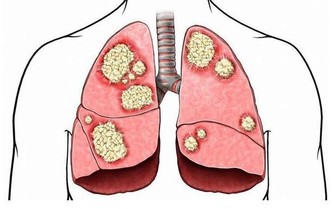

肺與大腸相表裡,肺氣虛也會影響大腸的蠕動功能,造成便秘。